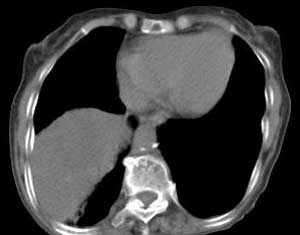

右肺门肿块影,中间段支气管以及右下叶支气管被浸润、堵塞,伴纵隔内淋巴结转移以及阻塞性肺炎。右肺中心型肺癌,堵的还很实在啊

考虑右中叶中央型肺癌合并右上肺肺内转移,胸膜转移.右中叶肺不张

右肺下叶中心性肺癌,阻塞性肺炎。

右肺下叶中心性肺癌,阻塞性肺炎

中央型肺ca伴肺不张,可以做支气管镜取病理

1,右侧中央型肺癌并右下肺不张及纵隔淋巴结转移;

右肺下叶中心性肺癌,阻塞性肺炎及段性肺不胀。纵隔淋巴结转移。右上肺陈旧性肺结核。

好象有钙化,考虑右下肺中央型肺癌(鳞癌)伴阻塞性改变,纵隔淋巴结转移;

右上肺渗出性改变;慢支肺气肿;胸廓畸形伴肺心病改变.

右肺下叶中心性肺癌,阻塞性肺炎及段性肺不张。纵隔淋巴结转移.

右肺下叶中心性肺癌,阻塞性肺炎及肺不张,纵隔淋巴结转移.

右中叶中央型肺癌合并右上肺肺内转移,胸膜转移.右中叶肺不张、肺内转移